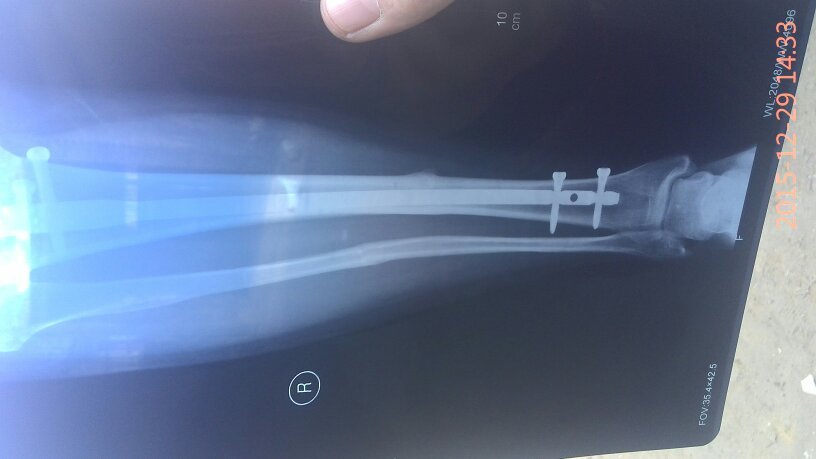

有骨科医生吗?我小腿骨折,上的钢板现在八个月了昨天复查医生说,骨头已经长好,可以取钢板了,我就是问 有骨科医生吗?我小腿骨折,上的钢板现在八个月了昨天复查医生说,骨头已经长好,可以取钢板了,我就是问问八个月了取是不是有点早,心里有点害怕,麻烦帮我看看告诉我,谢谢了…… 点击展开 匿名用户 2015-12-30 19:45 满意回答 怎么骨折的? 匿名用户 2015-12-30 20:55 宝宝知道提示您:回答为网友贡献,仅供参考。 为您推荐: 其他回答 你还是听医生的吧,时间太久了也不太好, 匿名用户 2015-12-30 20:54 没事了,别虚 匿名用户 2015-12-30 20:53 医生的话是对的 华雄40 2015-12-30 19:47 相关问题 小腿骨折钢板固定后,钢板折断且 小腿胫腓骨骨折只放了钢板没有复位这样好吗 我右小腿骨折,手术后有钢板,3个月了外伤口不愈合 是…